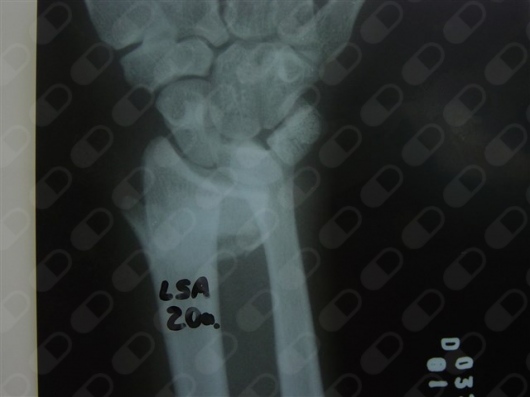

-ESCAFÓIDE: Tratamento da Fratura e da Pseudo-artrose do Escafóide com ou sem DISI e outras complicações, bem como Lesões Ligamentares da Mão e Punho, incluindo as do Ligamento Escafo-lunar do Carpo. Bennett, Rolando, Barton, Monteggia, Galleazzi e outras fraturas especiais ou comuns.